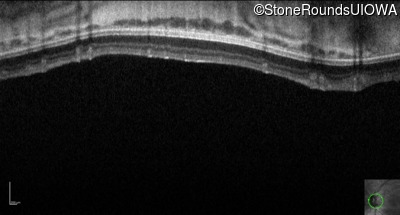

Optical Coherence Tomography - Right - 10/160 +1 sc

Exemplar / OCT Stack

OCT Stack